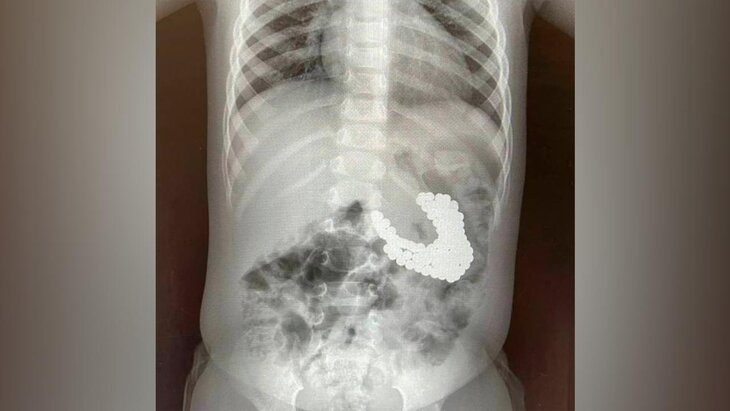

Врачи подмосковного ДКЦ имени Рошаля спасли 1,5-годовалого мальчика, который проглотил 130 магнитов и литиевую батарейку. Об этом пресс-служба Минздрава Московской области сообщила на сайте.

По данным ведомства, инородные тела в теле ребенка нашли после проведенного обследования. Извлечь магниты и батарейку нужно было как можно скорее, поскольку длительное нахождение таких предметов в организме может приводить к ожогам, перфорации внутренних органов, некрозу тканей и кровотечению.